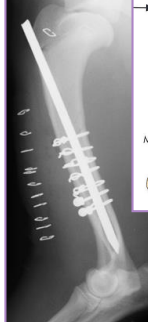

Interlocking Nail

What: IM pin + locking bolts proximal and distal

IM pin controls bending

Bolts control shear & rotation

Why: femur, tibia, humerus: limited to

$$, technically demanding, specialized

How:

Fills 80-90% of medullary canal

Place proximal and distal of break

Femur Fractures

Diaphyseal fractures (#1)

Tx: plate + screws, interlocking nail, IM pin + cerclage

ESF not recommended as no safe corridors

Tibia & fibula Fractures

Sx: Plate + screws, IM pin + cerclage, Interlocking nail, ESF